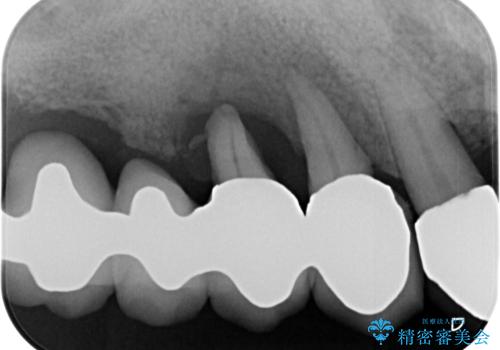

- 奥歯がぐらぐらして噛めないとのことで来院された患者様です。

ブリッジの土台となっている歯は全て抜歯が必要な状態であったため、事前に仮歯を用意して、極力抜歯と同時にインプラントを埋入し、速やかに仮歯を装着して噛めるように処置を進めて行くこととしました。

手前の歯は骨の欠損が著しいため、抜歯後暫く待ってから埋入を行うこととしました。